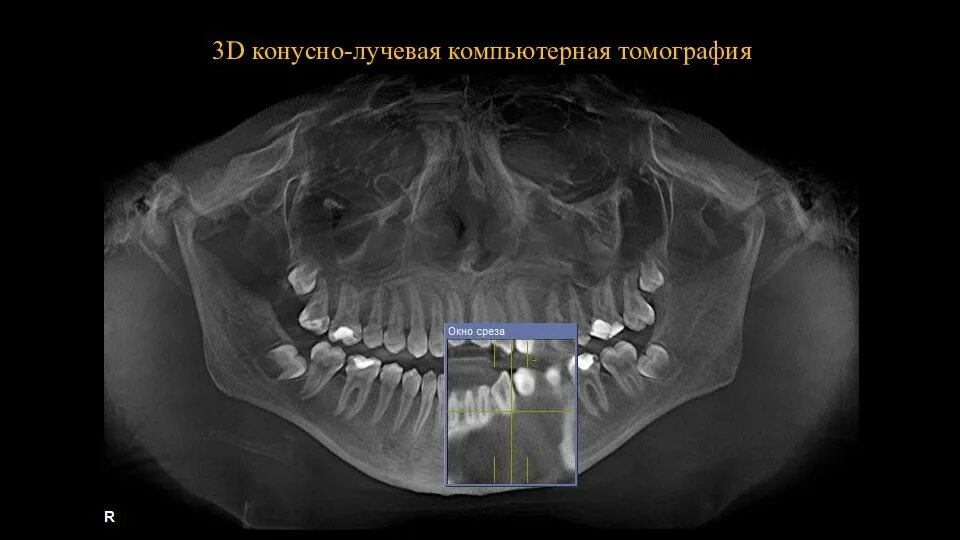

Кл кт